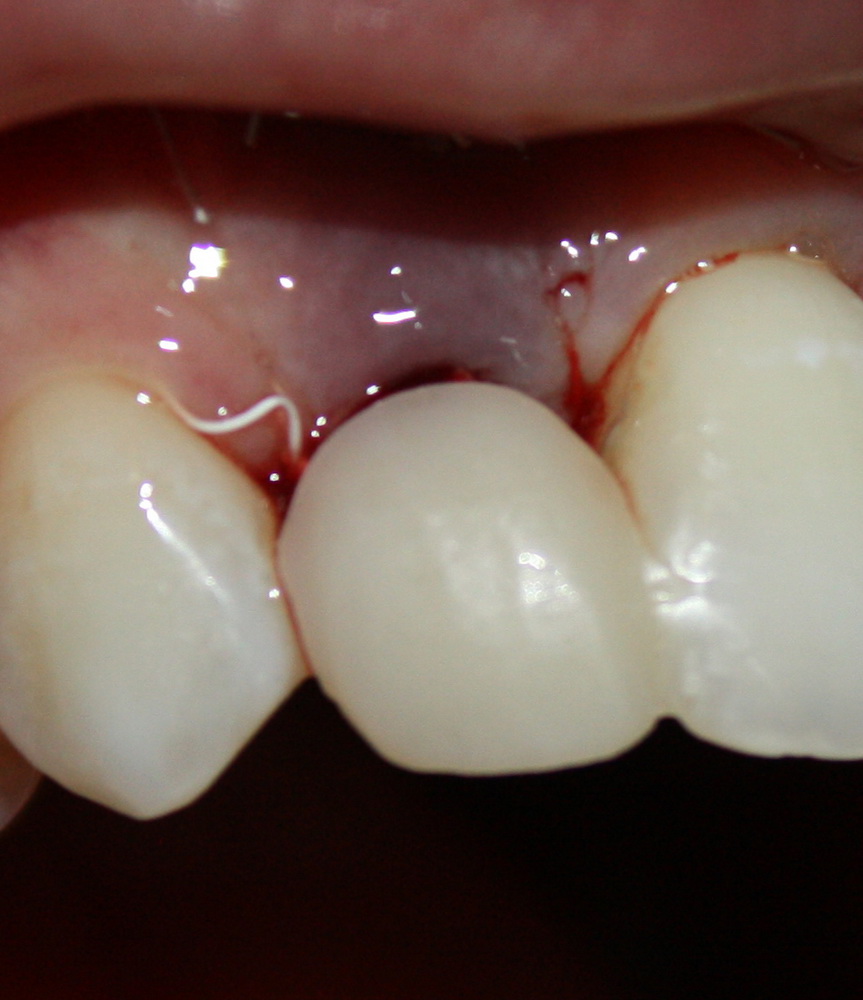

И удалили. Вместе с протезом. Через 15 минут после удаления Давид зафиксировал временный протез с опорой на импланты:

Уточню — это ВРЕМЕННЫЙ протез. При тотальном протезировании на имплантах, это почти необходимая вещь. Ибо заново настроить зубочелюстную систему, где вообще не осталось зубов, не так просто, как кажется. На это требуется время и ряд коррекций. К тому же, временный протез позволяет определить, как «работают» импланты под нагрузкой.